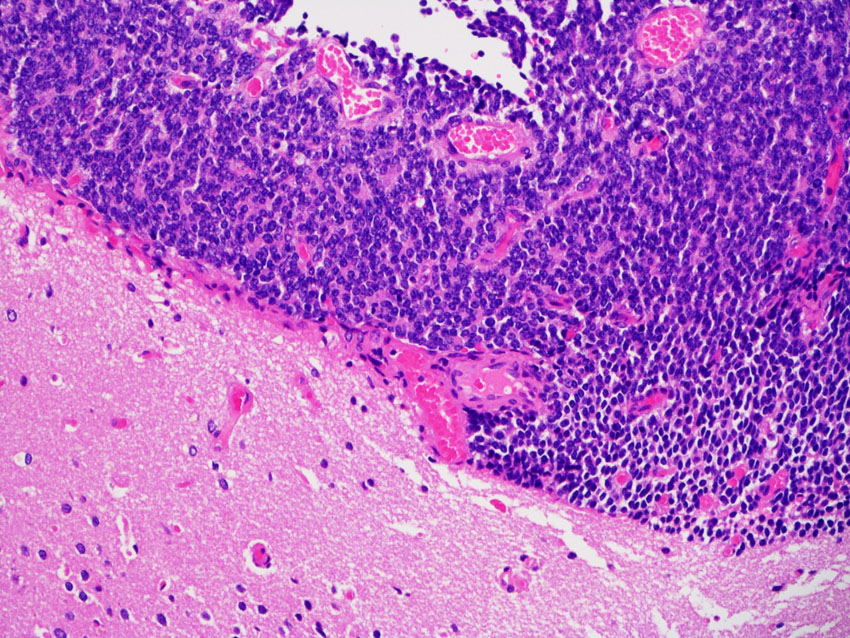

大脳表面に転移したPPTID グレード3の病理

PPTID グレード3の軟膜上(くも膜下腔)転移巣です。軟膜下の大脳組織には浸潤していません。PPTIDの特徴的な組織像は失われていますが,ロゼット形成が認められます。MIB-1染色率(左)は高く15%を超えます。転移巣はグレード4相当の性質を有していると評価します。